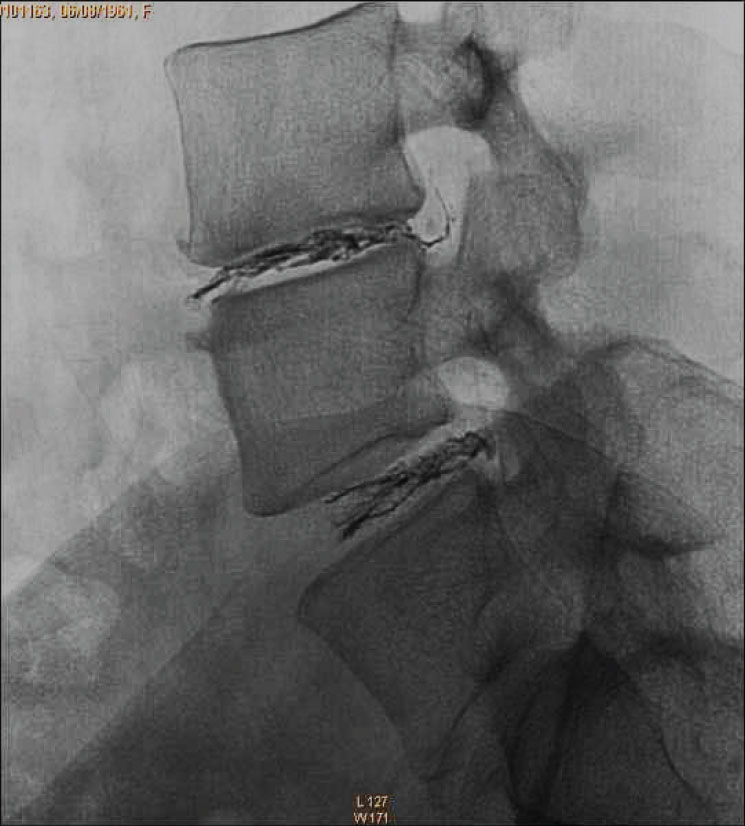

DiscoGel@ is a radiopaque gel implant, injected percutaneously into the nucleus pulposus.

• Micronized Tungsten allows the visualization of the gel progression under the fluoroscopic control where the injection flow can be observed.